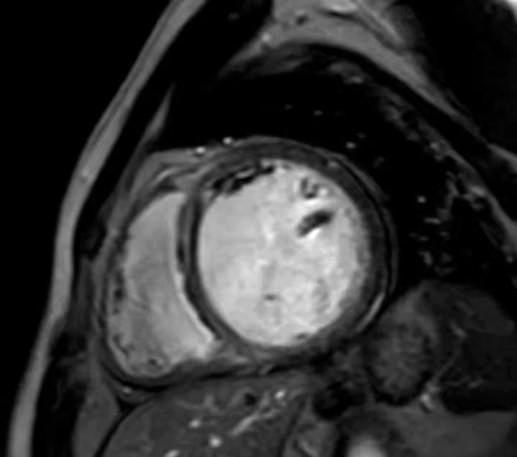

心脏延迟扫描